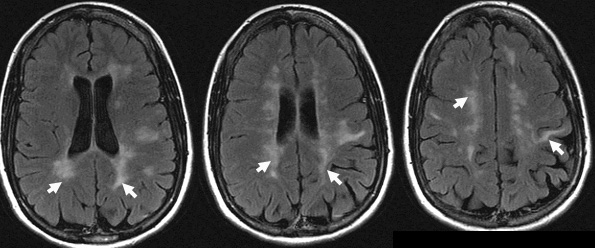

They are seen as bright lesions on T2 weighted or FLAIR series MRI.

Nonenhanced brain MRI (FLAIR) images show asymmetrical, abnormal high signal white matter lesions in the periventricular and subcortical areas